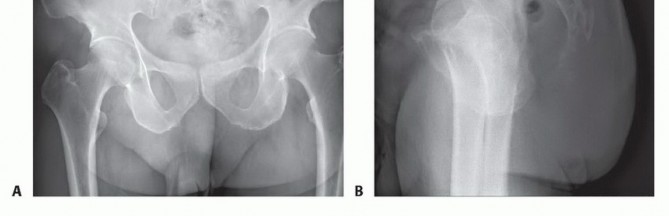

التصوير بالأشعة السينية العادية

قد تكون صور الأشعة السينية العادية غير واضحة في المراحل المبكرة من المرض. ومع ذلك، يمكن أن تساعد في تشخيص بعض الأورام، مثل الورم الحبلي الذي غالبًا ما يقع في الجزء السفلي من العجز، أو الأورام الكبيرة والمحللة تمامًا مثل ورم الخلايا العملاقة أو الكيس العظمي المتمدد في الجزء العلوي من العجز. تُعد الأشعة السينية ضرورية لإعطاء نظرة عامة ومتابعة ما بعد الجراحة.